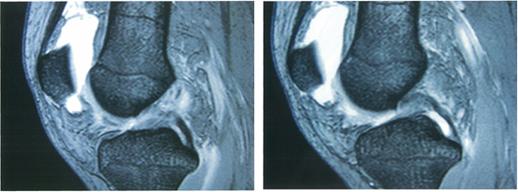

28歳の男性。野球のスライディングの際に右膝関節屈曲位で膝前面を強打し、疼痛が強く歩行不能になったため救急外来を受診した。治療開始から2週後のMRIを示す。この患者で陽性となるのはどれか。

-ostCE0nDl-wnZCuAl5tS

アプリヘンジョンサイン

外反ストレステスト

後方引き出し徴候

Lachmanテスト

Jerkテスト

28歳の男性。野球のスライディングの際に右膝関節屈曲位で膝前面を強打し、疼痛が強く歩行不能になったため救急外来を受診した。治療開始から2週後のMRIを示す。治療開始から3週後。疼痛は軽減したが筋萎縮が残存している。この患者に行うべき筋力訓練で誤っているのはどれか。ただし、図の矢印は運動の方向を示している。

ZKi8w7Oi6pkykP6E8wqCE